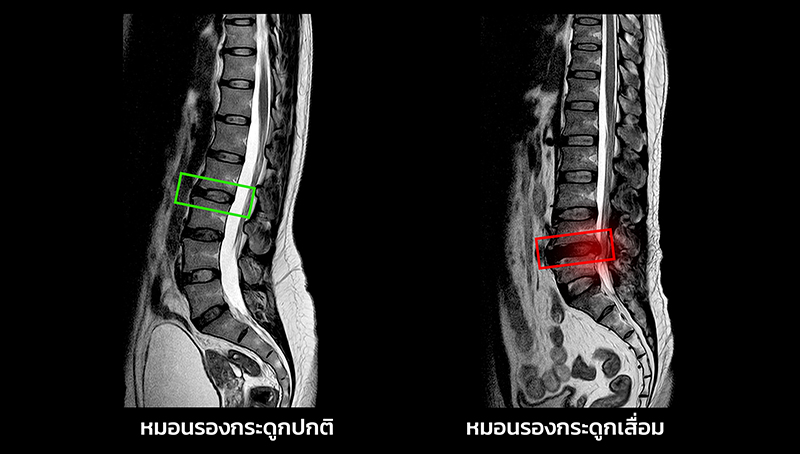

นพ.พร นริศชาติ แพทย์เฉพาะทางด้านกระดูกสันหลัง โรงพยาบาลเอส สไปน์ เผยว่า การนั่งผิดท่าเป็นเวลานานๆ ไม่เพียงแต่ทำให้เกิดอาการปวดหลัง แต่ยังสามารถเพิ่มความเสี่ยงต่อการเป็นโรคหมอนรองกระดูก หรือที่เรียกว่า หมอนรองกระดูกเคลื่อน หรือหมอนรองกระดูกทับเส้นประสาท ได้เช่นกัน โดยเฉพาะเมื่อท่าทางที่นั่งไม่เหมาะสมทำให้กระดูกสันหลัง และหมอนรองกระดูก ต้องรับแรงกดทับอย่างไม่ถูกต้องในระยะเวลานานๆ จึงอาจนำไปสู่ปัญหาหมอนรองกระดูกเสื่อม หรือการเกิดอาการหมอนรองกระดูกเคลื่อนที่มีผลต่อการทำงานของเส้นประสาท

การกดทับหมอนรองกระดูก การนั่งในท่าที่ไม่เหมาะสม เช่น นั่งค่อมหลัง หรือ โน้มตัวไปข้างหน้า จะทำให้เกิดแรงกดทับหมอนรองกระดูกที่อยู่ระหว่างกระดูกสันหลังในลักษณะที่ไม่ถูกต้อง ซึ่งจะทำให้หมอนรองกระดูกเสื่อมสภาพเร็วขึ้น หรือเกิดการเคลื่อนตัวออกจากตำแหน่ง ทำให้เกิดอาการปวดหลัง หรืออาจไปกดทับเส้นประสาทได้

กระดูกสันหลัง และหมอนรองกระดูก ไม่อยู่ในแนวตรงการนั่งในท่าที่ทำให้กระดูกสันหลังโค้ง หรือ ไม่ตรง เช่น การนั่งเอียงตัวไปข้างหนึ่ง หรือ โน้มตัวไปข้างหน้า จะทำให้หมอนรองกระดูกไม่สามารถรองรับแรงกดได้อย่างมีประสิทธิภาพ ส่งผลให้เกิดการเสื่อมสภาพหรือการยุบตัวของหมอนรองกระดูก

การนั่งนานเกินไป หากนั่งในท่าเดิมเป็นเวลานาน โดยไม่เปลี่ยนท่าทางหรือยืดเส้นยืดสาย จะทำให้กล้ามเนื้อหลังตึงเครียด และทำให้หมอนรองกระดูกต้องรับแรงกดจากการนั่งผิดท่าเป็นเวลานาน ซึ่งอาจเป็นสาเหตุที่ทำให้เกิดอาการหมอนรองกระดูกเคลื่อนหรือเสื่อมสภาพ

การกดทับเส้นประสาท เมื่อหมอนรองกระดูกเกิดการเคลื่อนหรือเสื่อมสภาพ การกดทับที่หมอนรองกระดูกอาจไปกดทับเส้นประสาทที่อยู่ใกล้เคียง ทำให้เกิดอาการปวดหลังที่ร้าวลงไปถึงขา (เรียกว่า Sciatica) หรืออาการชาและอ่อนแรงของขา

อาการของหมอนรองกระดูกเสื่อม

ปวดหลังส่วนล่าง เมื่อหมอนรองกระดูกเสื่อม อาจทำให้เกิดอาการปวดหลังส่วนล่าง ซึ่งอาจเป็นอาการที่รุนแรงหรือเรื้อรัง

อาการชาและอ่อนแรง หากหมอนรองกระดูกเสื่อมจนกดทับเส้นประสาท อาจทำให้เกิดอาการชา หรืออ่อนแรงในขา หรือแม้กระทั่งการเดินลำบาก

ปวดร้าวลงขา อาการปวดที่ร้าวลงขา (Sciatica) เป็นอาการที่พบได้บ่อยเมื่อหมอนรองกระดูกเคลื่อนหรือเสื่อมสภาพ โดยจะทำให้เกิดการกดทับเส้นประสาทที่ลงไปยังขา